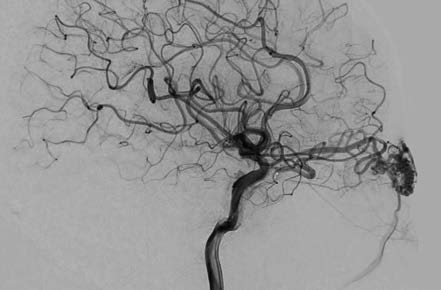

Figure 3 DSA imaging of orbital arteriovenous malformation

The feeding artery, vascular nidus, and draining vein are clearly visualized on angiography.

On CT imaging, orbital arteriovenous malformations often appear as poorly defined lesions with mixed-density signals, including hyperdense punctate or linear vascular structures. Some lesions may show hyperdense calcifications and hypodense areas of softening. Contrast-enhanced CT imaging often reveals worm-like enhanced clusters. MRI demonstrates the extent of the lesion and its anatomical relationships with great clarity. Both T1- and T2-weighted images exhibit characteristic flow voids, appearing as serpentine or globular low-signal areas within the lesion, surrounded by low signals from the feeding arteries and draining veins. Digital subtraction angiography (DSA) serves as the "gold standard" for diagnosing orbital arteriovenous malformations, providing detailed visualization of the feeding arteries, nidus, and draining veins.